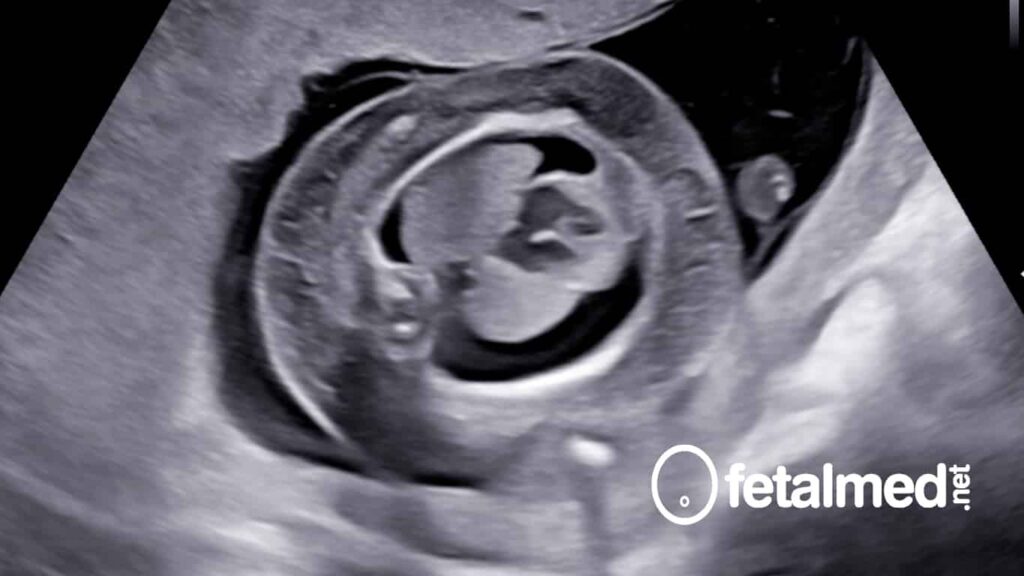

A hidropsia fetal é uma doença grave do feto que está associada a uma alta mortalidade perinatal que excede 72% em algumas séries. Tem muitas causas diferentes e muitas vezes uma origem multifatorial. A hidropisia fetal pode resultar de causas genéticas, metabólicas, inflamatórias ou de malformação associada. É plausível que a insuficiência cardíaca congestiva fetal por causa da alta pressão intracardíaca e perfusão tecidual inadequada possa resultar antes da morte fetal.